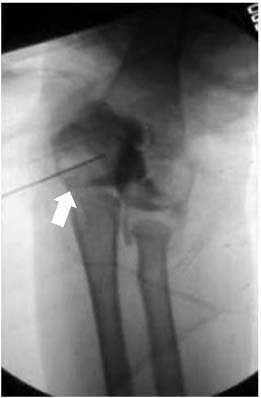

Fx: Fracture, Dx: Diagnosis, MCF: Medial condyle fracture, MRI: Magnetic resonance imaging, Intraop.: Intraoperative, OR/IF: Open reduction and internal fixation, LOM: Limitation of motion, ROM: Range of motion.